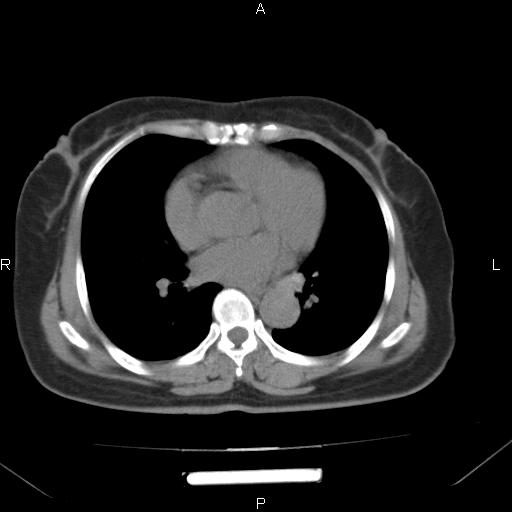

女、63Y 双眼睑下垂,早轻晚重。 胸腺瘤???

结果胸腺瘤